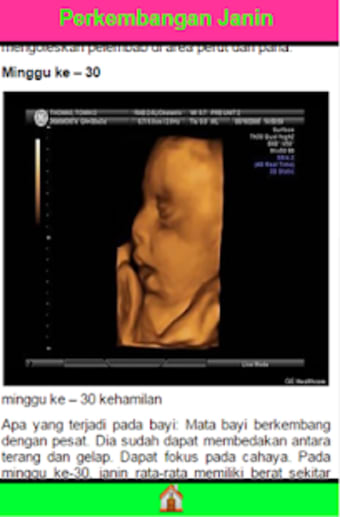

Perkembangan Janin 40 Minggu ist eine kostenlose Android-App, die von VillAndro in der Kategorie Bildung & Nachschlagewerke entwickelt wurde, speziell für die Unterkategorie Zeitschriften & Zeitungen. Diese App ist darauf ausgelegt, werdende Eltern durch die Phasen der fötalen Entwicklung während der Schwangerschaft zu führen. Sie bietet einen umfassenden Leitfaden zur Entwicklung des Fötus im Mutterleib für 40 Wochen. Die App ist informativ, benutzerfreundlich und vermittelt Eltern ein klares Verständnis für jede Entwicklungsstufe ihres Babys.

Die App ist perfekt für werdende Eltern, die über das Wachstum und die Entwicklung ihres Babys informiert und auf dem Laufenden bleiben möchten. Sie enthält detaillierte Informationen über die verschiedenen Phasen der Schwangerschaft und was in jeder Phase zu erwarten ist. Die App ist benutzerfreundlich, mit einer einfachen Benutzeroberfläche, die leicht zu navigieren ist. Insgesamt ist Perkembangan Janin 40 Minggu eine ausgezeichnete App für Eltern, die die Entwicklung ihres Babys während der Schwangerschaft überwachen und über die Veränderungen in ihrem Körper informiert bleiben möchten.